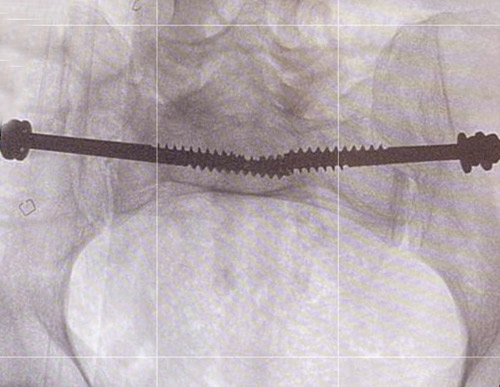

وقالت الوزارة إنه تم إرجاع، وتثبيت الخلع في المفصل العجزي الحرقفي لمريض في العقد السادس من العمر عن طريق وضع مسامير طبية باستخدام الأشعة التداخلية.

وأشارت «الصحة» إلى أن الطريقة المثلى لعلاج مثل هذه الكسور، هي تثبيت الكسر بالطريقة المغلقة لتسهيل تأهيل المريض ومساعدته على التحرك بشكل أسرع، موضحة أن الإجراء يتم عن طريق فتحة في الجلد من 2 إلى 3 سم تحت التخدير العام.